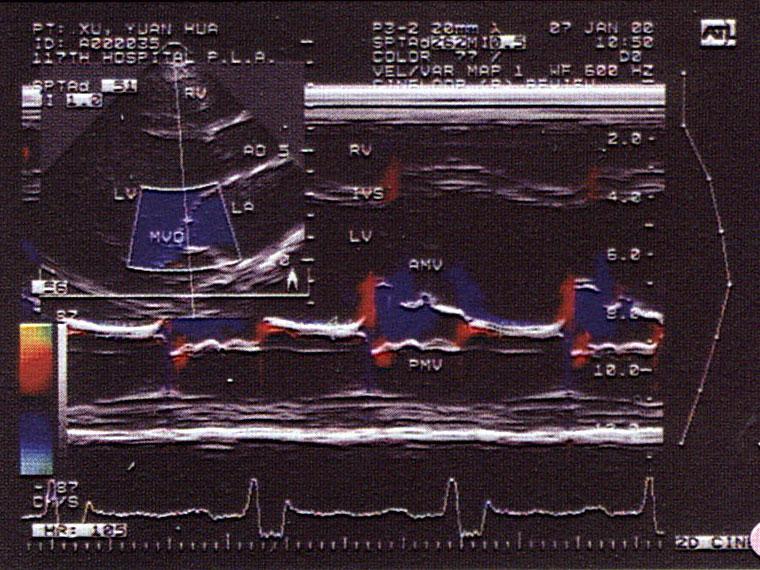

问题 该男,30岁,血压正常范围,心电图正常,T,T正常,该病例最可能的诊断?(?)

选项 A.冠心病 B.高血压心脏病晚期 C.甲状腺功能亢进型心脏病 D.扩张型心肌病 E.肥厚性心肌病

答案 D